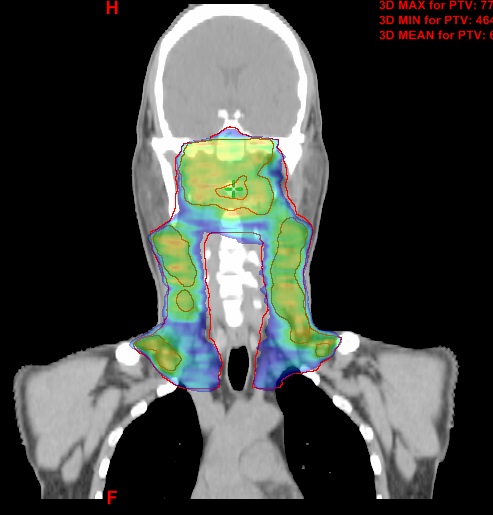

图2 后装插植植入治疗妇科肿瘤病例